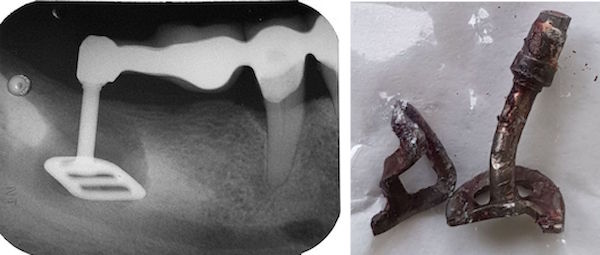

Beachte: Die Fraktur verläuft mesial 2 mm weit durch eine initiale Karies, zentral 6 mm neben einer Amalgamfüllung, und distal 3 mm lang mitten durch eine intakte Kompositfüllung. Diese ist mittig gespalten, aber nirgends vom Zahn abgerissen. Das Zentrum der Amalgamfüllung ist nicht gespalten.

Der Patient ist ein Heavy biter und kam seit Jahren immer wieder mal um Hyperbalancen einzuschleifen. Zudem war dieser +6 der letzte Molar links oben.

Auch auf diesem Röntgenbild ist weder die Hyperbalance noch der kleine Höckerwinkel mit der vertieften Zentrik sichtbar. Die initiale Karies war klinisch nicht sichtbar.